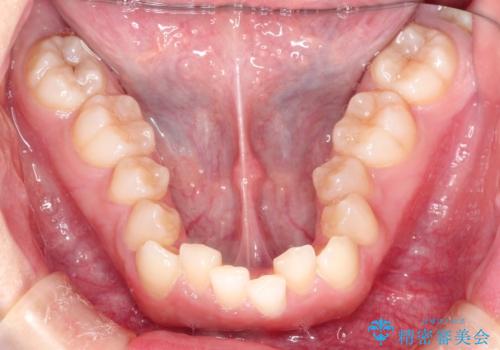

押しつぶされた歯列、アーチの拡大だけで非抜歯で改善した症例

初診時の歯並びの状態としては、上下ともに全体に及ぶの中等度以上のがたつき(叢生)があり、全額的に歯列のアーチが内側に押しつぶされた状態でした。

強い叢生がありましたが、抜歯は行わず上下顎ともに、主に歯列弓の拡大を行い叢生を改善しました。